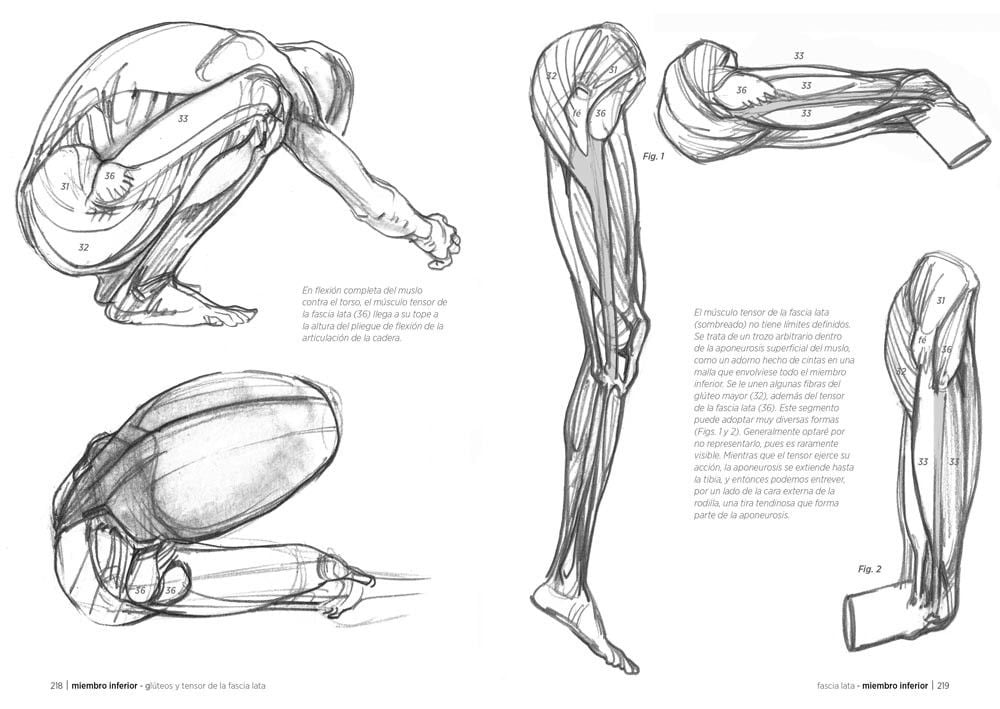

Si empiezas desde el trasfondo del artista, probablemente lo más recomendable sea checar libros de anatomía artística más especializados y de ahí escalar hacia publicaciones de corte mucho más médico, pues es ahí donde el dibujar ilustración médica entra en verdadero detalle acerca de todo tipo de sistemas, órganos y demás elementos de carácter biológico mucho más específicos.

- Anatomia para el artista de Daniel Carter

- Anatomía Artística (del que hasta donde se existen 6 tomos) de Michael Lauricella

- Anatomía humana para artistas de Gyorgy Feher (El ilustrador es András Szunyoghy)

- Dibujo de la anatomía y estudio del movimiento de Giovanni Civardi

Los de Anatomía Artística parecen ser del gusto de muchos y al parecer tienen precios accesibles, aunque si puedes conseguir cualquiera de estos libros valdrá la pena.